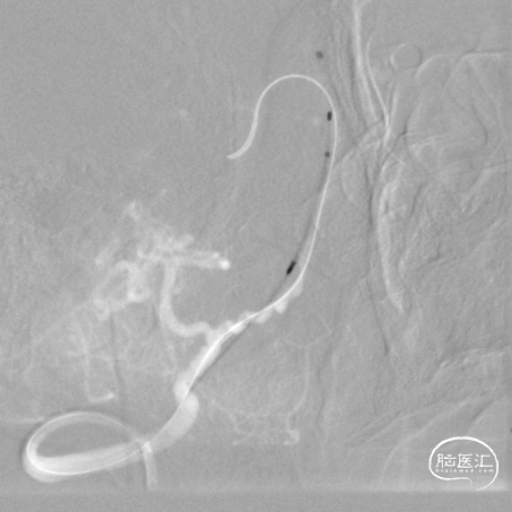

将微导丝头端置右侧大脑后动脉,沿微导丝引入2.0*10mm球囊,小心扩张狭窄段,撤出球囊后造影,原有狭窄较前稍好转,沿微导丝引入支架用微导管置于基底动脉,撤出微导丝,保留微导管,沿微导管引入3.5*15mm Neuroform EZ支架,缓慢释放,复查造影,狭窄较前明显好转,支架贴壁良好。

复查Dyna CT,颅内未见出血及造影剂外渗。

患者手术后头晕症状较入院时期明显减轻(可下地活动,活动时无明显发作,四肢活动自如,一般情况可)。